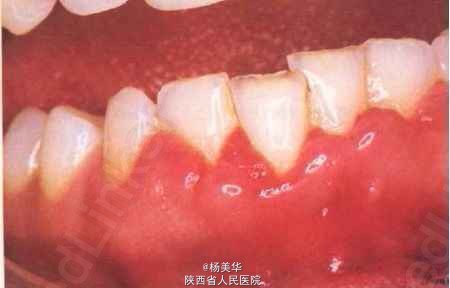

主诉:患者因下前牙出血一周要求诊治。 病史:患者近一段时间来刷牙及咀嚼食物容易出血,至今有一周左右,现要求诊治。

检查:下切牙颈部牙石1度沉积,牙龈充血发红,质地松软,边缘厚钝,龈乳头圆钝,肥大面光亮,龈沟深度3mm,轻探出血,无附着丧失。

诊断:下切牙边缘性龈炎。 鉴别诊断:1,早期牙周炎,有牙周袋,牙槽骨吸收;2,血液病,应与全身性疾病鉴别如白血病,血小板减少性紫癜等;3,坏死性龈炎,虽以牙龈出血为主要症状,但其牙龈边缘坏死如虫蚀状,坏死区出现灰褐色假膜,伴有疼痛和特殊的腐败臭味;4,爱滋病相关的龈炎。 治疗计划:1,去除病因,洁治术;2,药物治疗,双氧水冲洗,上碘甘油;3,维护治疗,掌握正确刷牙的方法,定期洁治,保持口腔卫生。